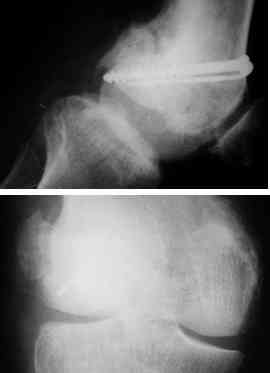

I opened it up from the lateral aspect.

Freed up the non-union site with minimal disturbance to the posterior and lateral soft tissue attachments on the lateral condyle fragment.

Applied a distractor between femoral shaft and tibia, to create a space on the lateral aspect.

This brought the lateral condylar fragment into a position that seemed to be reasonably well aligned, but showed up a bone gap.

This was fixed temporarily, bone grafted with tricortical struts, and fixed by two cancellous screws. The fragment was not large enough to afford any fixation to a plate or such implant, and the screws held it compressed well to the rest of the distal femur.

Post-op - limb is well aligned, rom 0-30, but I am not pushing that right now, for the next two or three weeks.

Further plan - hope that the screws hold the fragment appropriately till union, but if the stability on table is anything to judge by, that should not be a problem.

Quadricepsplasty after a year or so, to restore flexion.

Pictures attached.

A good job, though personally I would have preferred the screws a bit longer.